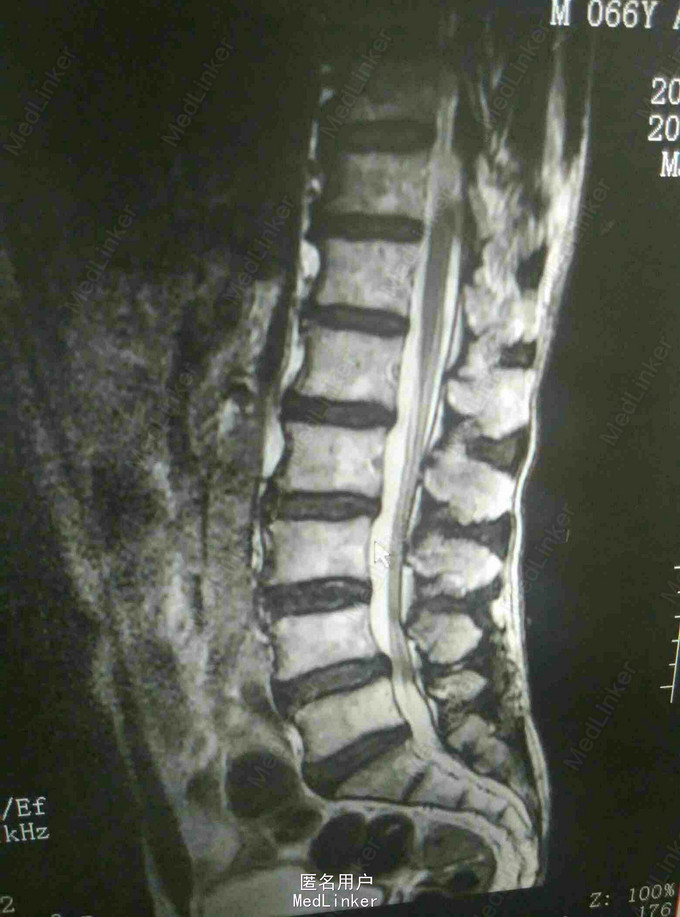

反复腰痛5年,加重伴跛行10余天 患者老年男性,5年前无明显诱因出现腰痛,休息后缓解,数年来反复发作,自行外用膏药对症治疗。近10余天来患者腰痛明显加重,伴跛行,右下肢疼痛,于当地医院就诊摄片提示腰椎退变,为进一步治疗入我院。

查体:腰4~5棘突及骶部压痛,无明显叩击痛,右大腿外侧疼痛,右足背外侧感觉减退,双下肢肌力正常,双侧直腿抬高实验阴性。 辅查:外院X线片提示腰椎退变 我院核磁提示腰4-5关节突增生内聚,椎间盘后突压迫硬膜囊及神经根

诊断:腰椎管狭窄 治疗:腰椎后路减压植骨内固定术